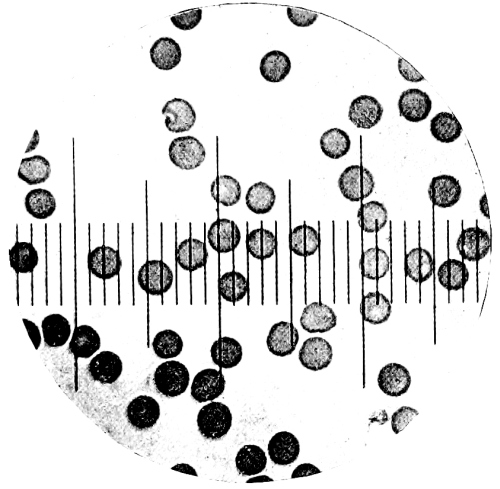

8. Measurement of Blood Corpuscles (human) 97

9. Measurement of Blood Corpuscles (sheep) 97